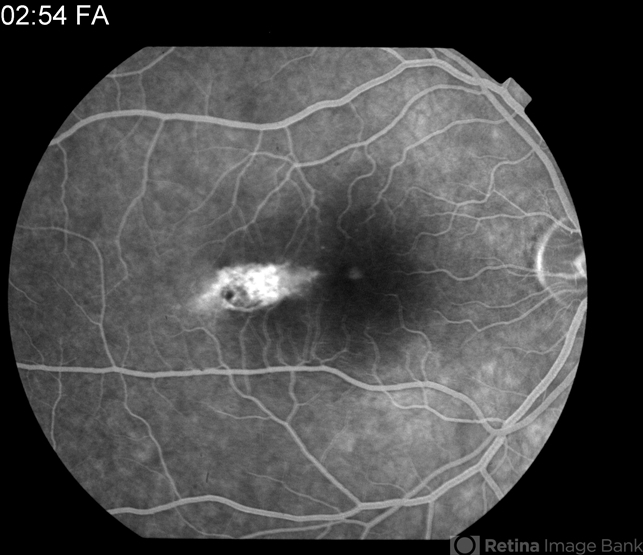

- torpedo maculopathy, choroidal nevus

- Fluorescein angiography of a 47-year-old female with torpedo maculopathy- atypical choroidal nevus.